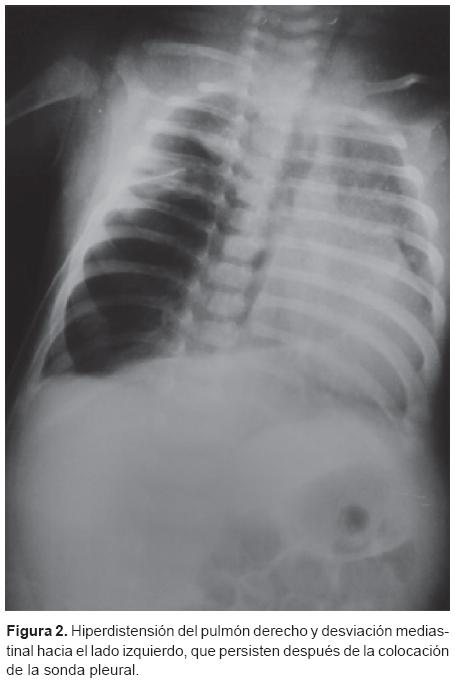

Se trata de un paciente femenino de 2 meses de edad que desde su nacimiento en el Hospital Regional de Zona del Instituto de Seguridad y Servicios Sociales de los Trabajadores del Estado (ISSSTE) en La Paz, Baja California, México, presentó un cuadro caracterizado por dificultad respiratoria severa acompañada de tos seca, estridor espiratorio, cianosis central durante la alimentación, además de la presencia de tiraje intercostal y disociación toraco-abdominal, lo que se catalogó como un proceso neumónico; se manejó con múltiples esquemas de antibióticos y con la colocación de un sello pleural en dos ocasiones para resolver un supuesto neumotórax y un derrame pleural como complicaciones del proceso infeccioso. Se realizaron estudios de gabinete y se observó en la radiografía simple de tórax una imagen de hiperlucidez y atrapamiento de aire en el pulmón derecho, atelectasia en el pulmón contralateral y desplazamiento del mediastino hacia el lado izquierdo (Figuras 1 y 2). Se complementó el estudio de imagen con TAC de tórax y se encontró en los cortes superiores una zona enfisematosa aparentemente del lóbulo superior derecho (Figura 3) y en los cortes inferiores parénquima pulmonar normal, imágenes compatibles con ELC derecho. Se decidió enviar a la paciente del Hospital Regional de Baja California a un hospital de alta especialidad en la Ciudad de México para realizar la corrección quirúrgica del padecimiento. Sin embargo, durante el traslado aéreo, la paciente presentó un evento de cianosis e incremento de la dificultad respiratoria, por lo que descendió de manera urgente en la Ciudad de Guadalajara, Jalisco, México, y se trasladó al Hospital Regional Dr. Valentín Gómez Farías (HRVGF).

La paciente evolucionó de forma favorable. El pulmón derecho residual presentó una buena expansión posquirúrgica y se centralizaron las estructuras mediastínicas (Figura 4). Se retiró la sonda de la toracotomía al sexto día después de la cirugía. También se corrigieron la sepsis y las alteraciones hematológicas.